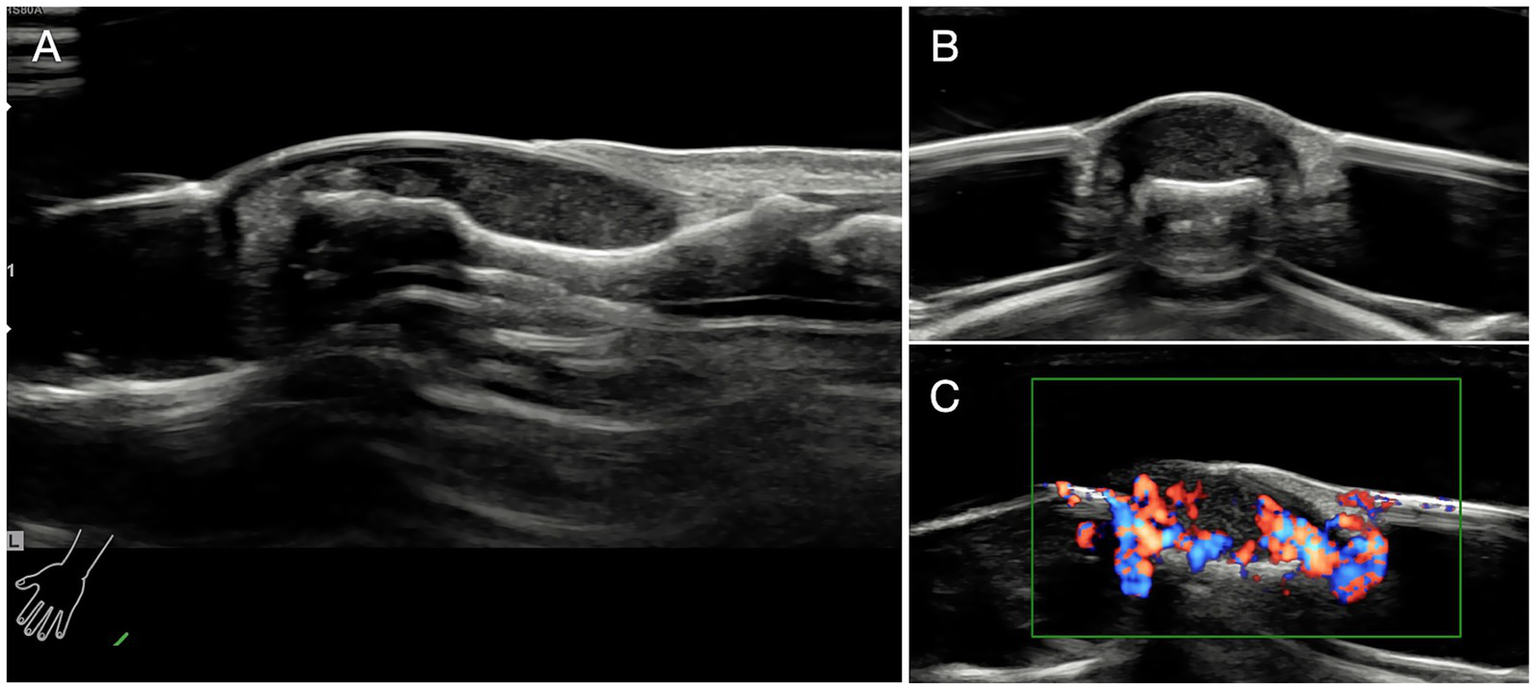

Ultrasonic investigation were also taken to confirm the diagnosis and localization (Figure 3) (25, 26).

Figure 3

Ultrasonic investigation. (A) Glomus tumor exhibited regular shape and clear margin under ultrasonic examination. Tumors were low-echo without lateral shadows locating in the subungual area. (B) The ultrasonographic view of coronal section of the affected finger. (C) Abundant blood flow and vessels in and out of the tumors were observed.